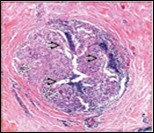

Figure 2.Granulomatous mastitis with articulated epitheloid cell granuloma, lymphocytic, plasma cell and neutrophilic infiltration10.

Core needle biopsy of idiopathic granulomatous mastitis enunciates multiple aggregates of non- caseating epitheloid cell granulomas within and encompassing breast lobules, constituted of epitheloid histiocytes, lymphocytes, neutrophils and multinucleated giant cells. Granulomatous inflammation is predominantly lobulo-centric. The inflammation is preponderantly composed of lymphocytes, plasma cells, epitheloid histiocytes, multinucleated giant cells and neutrophils. Neutrophils can configure micro-abscesses and encompass vacant micro-cystic cavities, morphological features which are in common with cystic neutrophilic granulomatous mastitis. Non specific lobulitis along with a lymphoid and plasma cell infiltrate accompanies the granulomatous inflammation. Necrosis is usually absent. Neutrophilic micro-abscesses can be accompanied by fistula formation 4, 5.

Multinucleated giant cells are detected in an estimated three fourths (78.5%) instances. Plasma cells are discernible in around half (53.9%) of the subjects and usually appear at the margins of cystic vacuoles with centric accumulation of neutrophils within the granulomas.